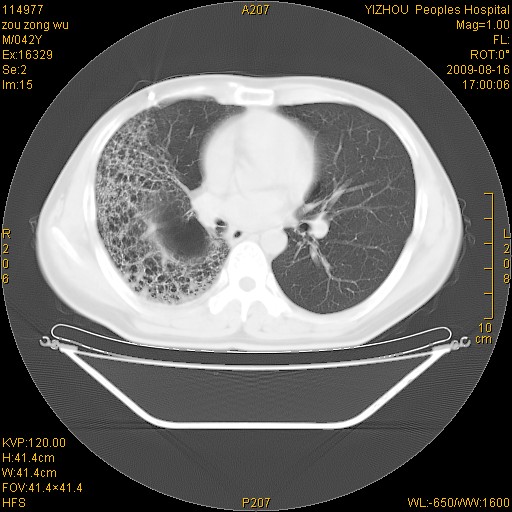

以下是引用zjzjr在2009-8-17 10:42:00的发言:[br]右侧间质性肺炎伴纤维化,右肺下叶肺囊肿伴感染(不除外外伤后引起),右肺野及胸壁软组织\\肝内见多发斑点状,中枪了吧.右侧胸膜肥厚\\粘连.